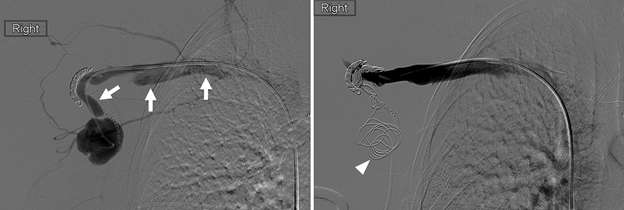

Figure 5B. Pseudoaneurysm. Pre-treatment selective catheter-directed digital subtraction angiography (left, middle) in the interventional suite confirmed the presence of a large pseudoaneurysm (arrows) fed by a branch of the right axillary artery. Post-treatment angiography (right) status post coil embolization of two identified feeding branches (white arrowheads) demonstrates faint residual filling of the sac (asterisk). During the intervention, it was noted that the pseudoaneurysm had an associated outflow tract with brisk drainage via the right axillary vein (yellow arrowheads), consistent a concomitant iatrogenic arteriovenous fistula (AVF).

Figure 5C. Pseudoaneurysm. Following transarterial coil embolization, venous access was obtained, and digital subtraction venography was performed confirming right axillary venous outflow from the pseudoaneurysm (left, arrows). Embolic coils (right, arrowhead) were then deployed within the sac, and post-treatment venography demonstrated no further retrograde transvenous filling of the pseudoaneurysm.